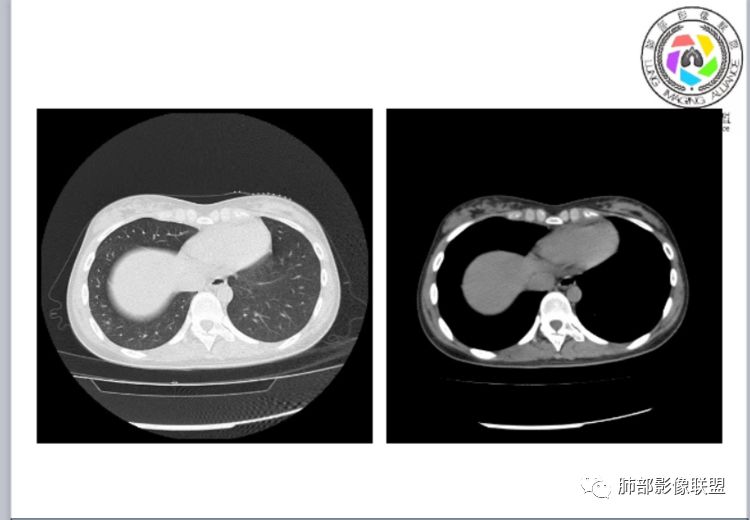

小微:右肺下叶斑片状密度增高影,抗炎治疗6天后复查,双肺下叶出现斑片状密度增高影,排除炎性病变,D2聚体特别高,考虑肺栓塞,肺梗死,建议增强扫描。王开金江津中心医院呼吸科:@岳微-辽宁PLA234医院放射科?支持,患者年轻女性,胸痛主诉,使用雌激素,高危人群,心率快,d二聚体升高,右下叶斑片加肺动脉明显增宽,抗感染无效,要考虑PTE,建议肺动脉ctpa。傅昌瑜:19岁,女性,右侧胸痛2天,发热以中度热为主,D—二聚体升高,肺动脉主干增宽,病灶位于胸膜下,抗感染后增多,近来有服用炔雌醇环丙孕酮片2周期史,诊断:肺栓塞,下一步完善肺CTPA检查。阿仙奴:青年女性,急性起病,胸痛入院,月经不调史,目前服用孕酮片。流感抗体阳性,d二聚体升高,无低氧血症。右肺下叶基底段胸膜下磨玻璃样改变,肺动脉增宽,治疗过程出现发热,复查左下叶胸膜下新发病灶。考虑:肺栓塞(服用孕酮相关)?奔跑的37°Doctor(陆喜红 ) :年轻女性,胸痛 急性病程,有服用雌激素避孕药史(是否有血液循环的改变,高凝状态),实验室D二聚体很高(也是提示血液高凝状态) ,第一次CT,右下肺胸膜下斑片状密度增高模糊影,肺动脉形态密度未见明显异常,抗炎后复查,肺动脉干及其分支,感觉增粗了一点,局部形态有点饱满,双下肺胸膜下片状影增多,锁定肺动脉栓塞应该不会错,建议CTA检查飞鹰行动:青年人,女性,右肺下叶斑片状密度增高影,抗炎治疗6天后复查无好转,,双肺下叶出现斑片磨玻璃影,主肺动脉增粗,结合患者服用的药物和D2聚体特别高,考虑肺栓塞,建议CTA。李:口服避孕药,有危险因素,肺动脉较主动脉增宽,D二聚体增高,胸膜下片状影,考虑肺栓塞;@晨义工张帅,医附属潞河医院呼吸?是否痰中带血很关键,不知有没有张帅:患者入院后第七天出现痰中带血风之子:病程中有发热,D—二聚体升高,肺动脉主干增宽,病灶分布于胸膜下,抗感染后增多,结合服药史诊断:肺栓塞,建议CTPA检查。不支持的地方是没有低氧血症,不明白为什么第二次复查ct双侧乳腺不对称,按理乳腺炎多见于哺乳期张帅:大家方向都在考虑肺栓塞:我提问两个问题:1 周围毛玻璃怎么回事?2左下肺小叶间隔增宽怎么回事?笨丫头:周围的磨玻璃应该考虑是肺梗死后出血渗出,同时合并机化性炎症小叶间隔增宽,我考虑应该是梗死后炎性渗出wonderful:我不支持肺栓塞 不能解释发热原因

笨丫头:肺栓塞也会发热呀王江涛:肺内子宫内膜异位症,合并梗死出血Lenle董:外围渗出性改变,出血?左下肺的支气管镜不会看张帅:呼吸困难比较难判断,尤其对于一个有胸痛的患者来说@唐大川新沂市人民医院呼吸科风之子:对,要警惕子宫内膜异位症岁月:病史:女,19岁;右侧胸痛2天;血常规17.4,中性粒75.7%,右下肺斑片影;月经不调,雌激素?治疗;D2高,3974.78,支气管镜阴性。治疗方式,抗炎。病史诊断方向:肺栓塞?影像:首先找肺栓塞影像。6天后CT可疑肺栓塞;作者量肺动脉23.7mm,提示什么?好像和同层面主动脉宽度相当,先心病?肺血无明显改变?双肺斑片影,左侧磨玻璃,边界清楚,还有些散在不清楚,左侧为甚,胸膜下贴,三角形?左侧少了胸水;诊断:肺栓塞;鉴别:先心合并肺栓塞?肺炎。

张帅:好多老师都在说肺动脉增宽。肺动脉增宽标准是多少?程磊:29。或者比同层主动脉比值大于等于1

张帅:我量的虽然不标准,但不到24

CT平扫及间接征象:

1、一个或多个胸膜下斑片高密度影(梗死、出血、肺不张、肺水肿、炎性渗出),典型为胸膜下楔形影 ,尖端指向肺门

2、肺动脉高压(中心肺动脉扩张),有时可见肺动脉区高密度影。

3、肺血减少

4、马赛克灌注

5、膈肌升高、胸腔积液、心包积液

3.影像:病变胸膜下多发斑片影,提示与血管有关,早期病变为渗出,应该是早期的炎性渗出,病灶抗感染治疗后实变区增多、变大,临床症状又出现咯血,CT上应该合并了肺泡出血、梗死、肺不张及肺水肿;